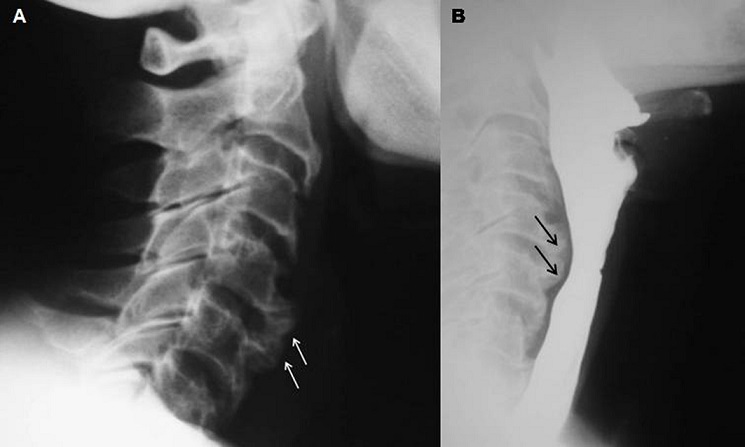

La maladie de Forestier ou hyperostose ankylosante sénile rachidienne est une maladie rhumatologique d'étiologie inconnue décrite pour la première fois en 1950 par Forestier and Rotes-Querol. Elle est caractérisée par une ossification des ligaments paravertébraux et des enthèses périphériques. Le plus souvent asymptomatique, la maladie de Forestier est de découverte fortuite sur des radiographies standards. Plus rarement, elle se manifeste par des douleurs cervicales, une raideur rachidienne ou une dysphagie. Nous rapportons l'observation d'une patiente âgée de 58 ans, aux antécédents de diabète 2, qui consultait pour une dysphagie haute aux solides évoluant depuis 6 mois, associée à des cervicalgies. La dysphagie s'améliorait par la flexion du rachis cervical et s'aggravait par l'extension. Il n'y avait pas de dyspnée, ni de dysphonie, ni d'altération de l'état général, ni notion de fausses routes. La mobilité rachidienne cervicale était conservée. Les examens ORL et neurologique étaient sans particularités. Le bilan biologique ne montrait pas de troubles métaboliques ni de syndrome inflammatoire. Les radiographies standards du rachis cervical révélaient des ostéophytes cervicaux antérieurs en regard de C4-C5 et C5-C6. Le transit oe'sogastroduodénal objectivait une compression de la paroi postérieure de l'oesophage en regard des ostéophytes. Le traitement était symptomatique reposant sur des anti-inflammatoires non stéroïdiens, des antalgiques et une rééducation adaptée.